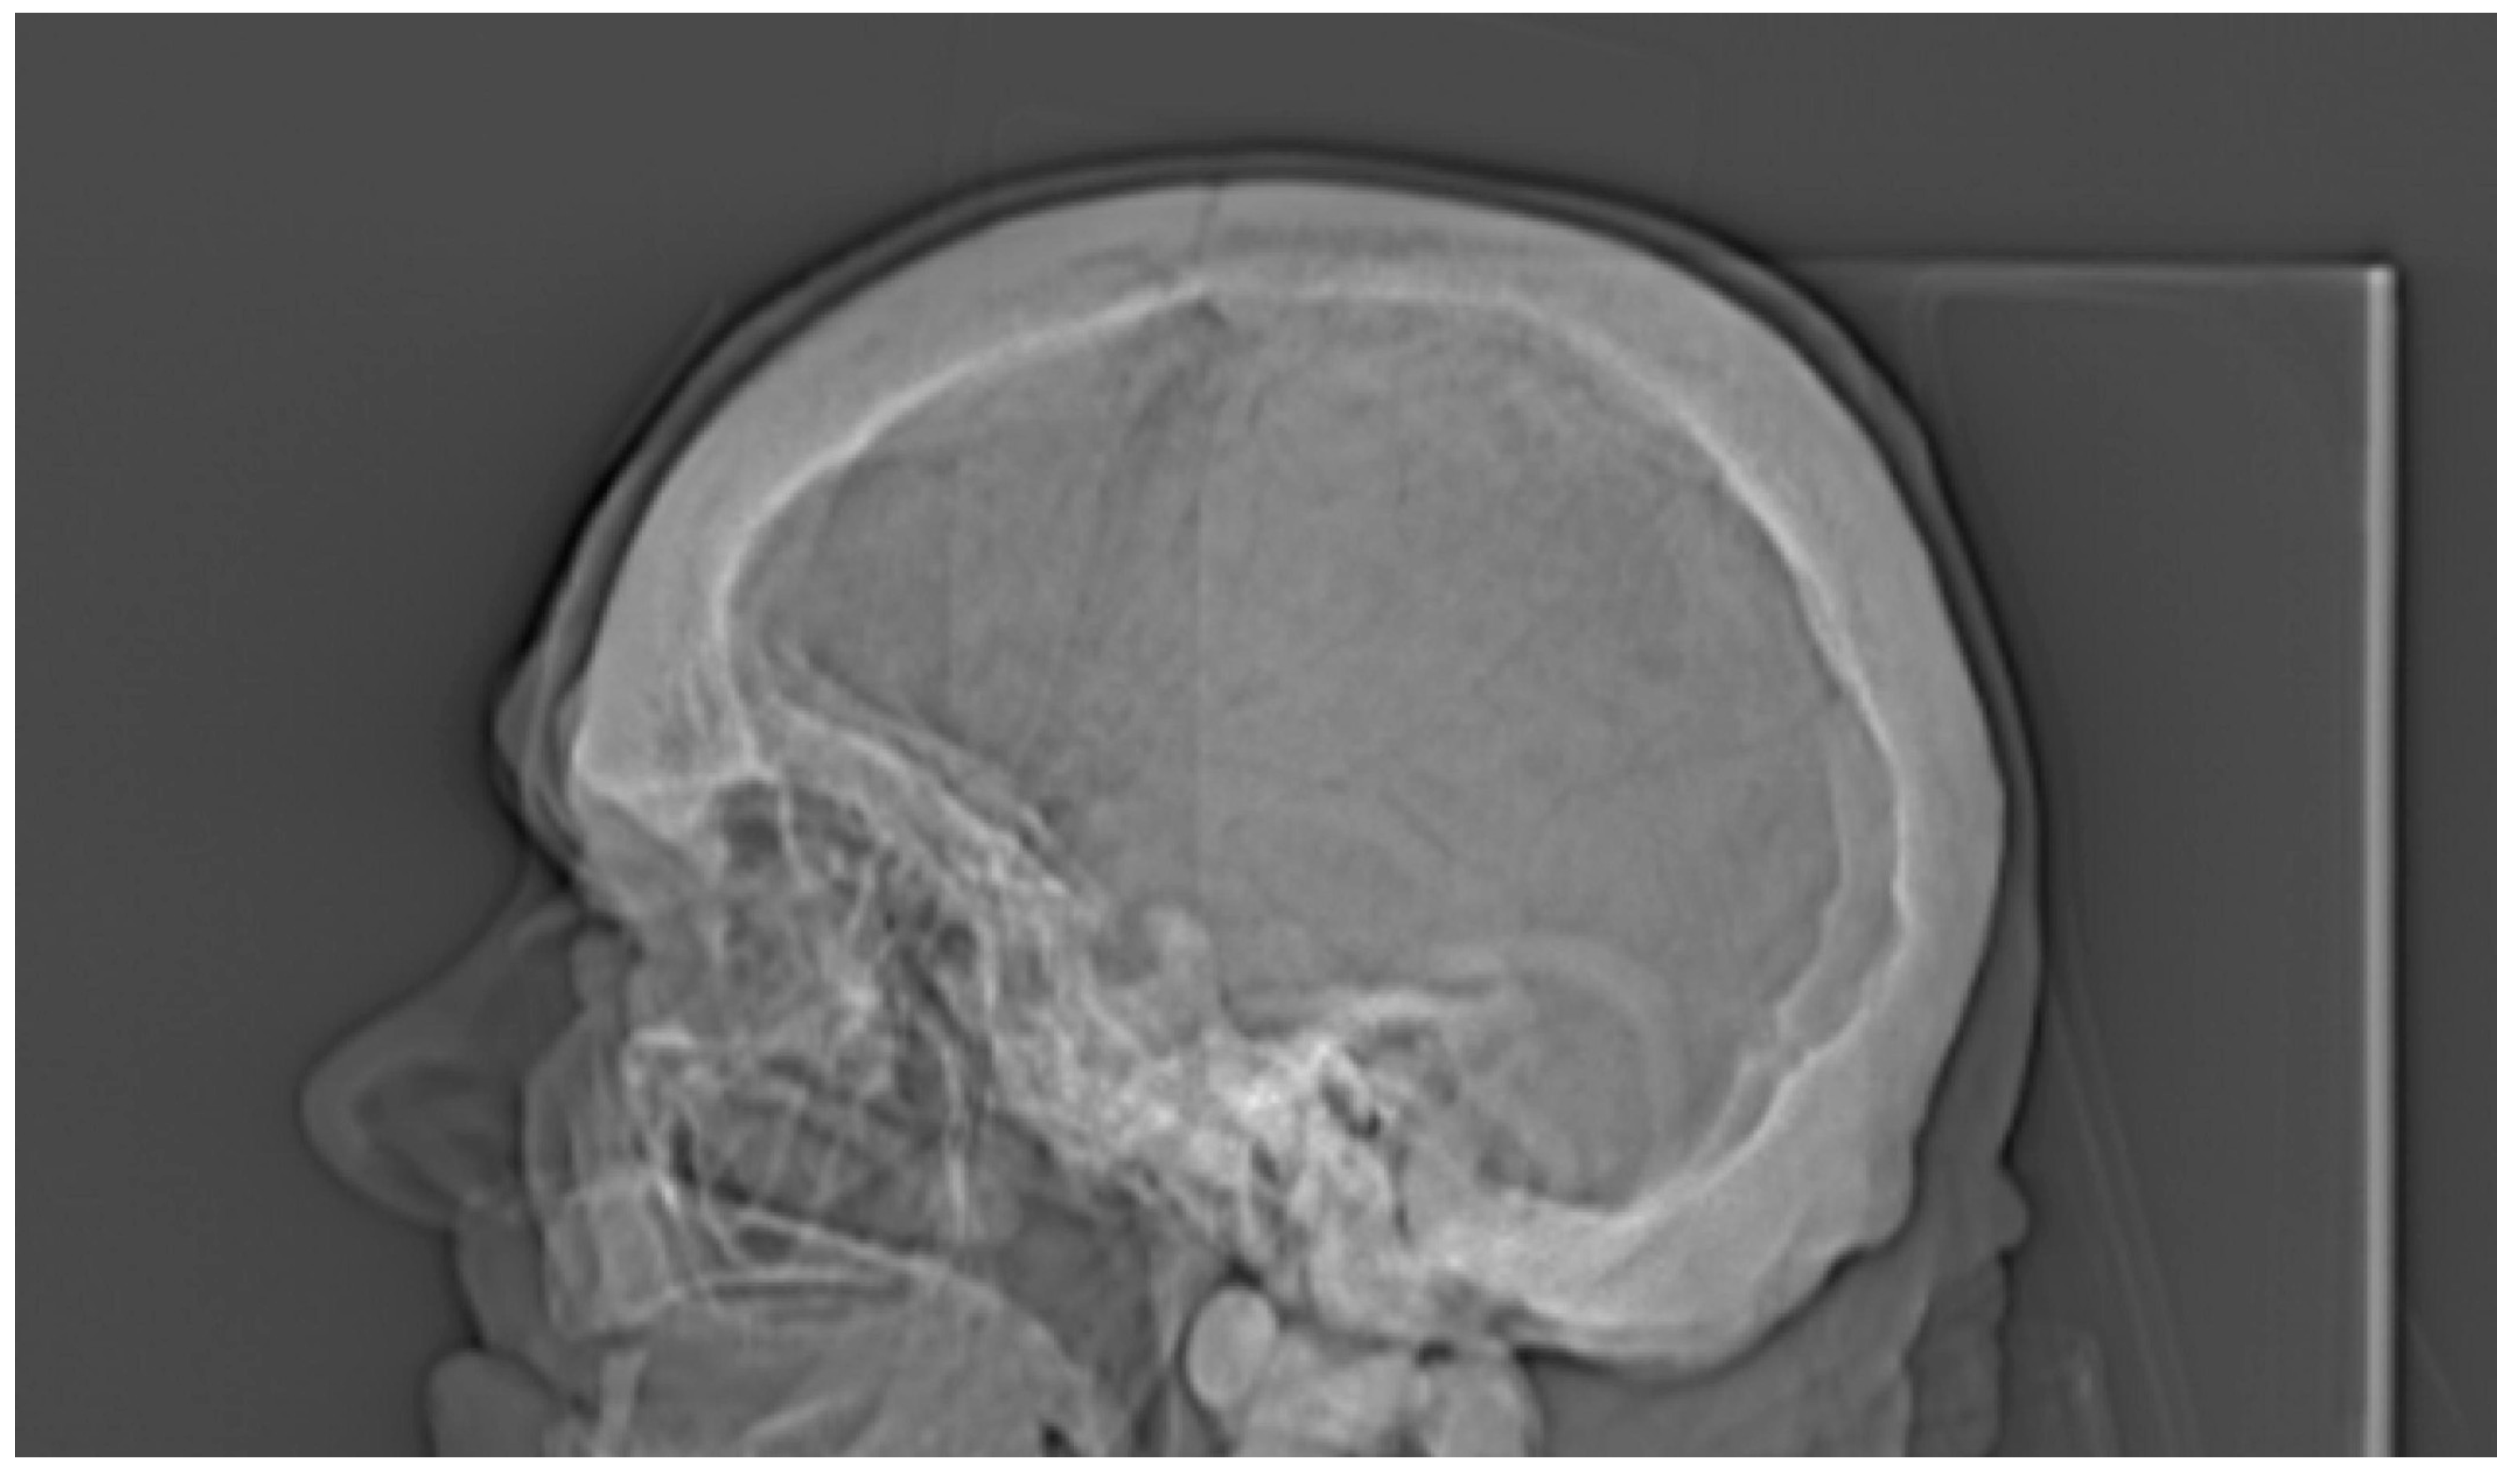

| Cranium | |||||

| 50% of cranium height | - | - | - | - | 2.111 |

| Radiological Feature | ADO Type I | ADO Type II | ADO Type III | Presented Case |

|---|---|---|---|---|

| General osteosclerosis | + | – | + | + |

| Skull vault osteosclerosis | + | – | + | + |

| Skull base osteosclerosis | – | + | – | + |